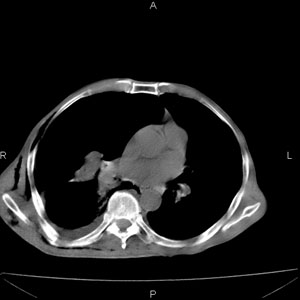

患者男,77岁,于3日前从树上摔下,头部查ct示蛛血,硬膜下出血,上腹部ct未见明显异常,右侧胸腔积液,左侧如常。肺部拍片示右侧肋骨多发骨折住院后今日来查肺部ct,我看到的是1。右侧胸腔血气胸并右肺上叶,中叶压缩性肺不张,2。右肺下叶肺挫伤并多发肋骨骨折,肌内及皮下积气3。左侧少量胸腔积液,我想请教的是3天前左侧胸腔里没有积液今天怎么出现了呢,是什么原因呢?请讨论。

回复楼主   左侧液气胸,液体来源1、肯定有血液成分,多少不一定。2、胸膜腔渗液,由于肺压缩、活动度下降,肯定胸膜吸收有问题,导致积液增多。

支持楼主诊断。液体来源:1、血液成分,外伤所致。2、胸膜腔渗液—由于肺压缩、活动度下降,肯定胸膜吸收有问题,导致积液增多。

考虑外伤性迟发性胸腔积液。

右侧液气胸,胸膜创伤、肺组织挫伤,渗出属正常反应。

右侧多发肋骨骨折,同侧液气胸